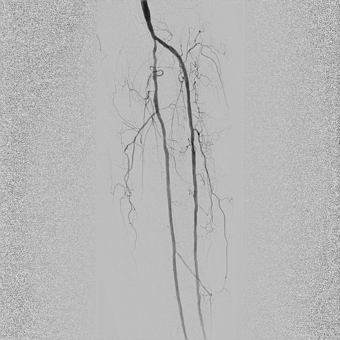

— У пациентов с синдромом диабетической стопы, к сожалению, чаще выполняется ампутация конечности, чем попытка восстановления кровотока в пораженной конечности. Хотя на сегодняшний день возможности сосудистой и эндоваскулярной хирургии позволяют если не сохранить конечность целиком, то хотя бы сберечь ее опорную функцию, тем самым сохранив пациенту мобильность, а значит и высокое качество жизни. Эта пациентка поступила к нам с сухой гангреной без инфицирования 1, 2, 3 пальцев правой стопы 2А степени по классификаци Техасского университета. Была предпринята попытка эндоваскулярной реконструкции пораженных артерий бедра и голени, критическое сужение или окклюзия которых и приводит к синдрому диабетической стопы и необходимости ампутации. Нами была выполнена реканализация подколенной, передней большеберцовой артерии и малоберцовой артерии правой ноги. Полностью пройти подошвенную дугу и заднюю большеберцовую артерию не удалось, но, несмотря на это, полностью был восстановлен кровоток в стопе и пальцах.

![]() Окклюзия артерий голени |

![]() Реканализация передней большеберцовой артерии и малоберцовой артерии; проходимость артерий голени восстановлена |